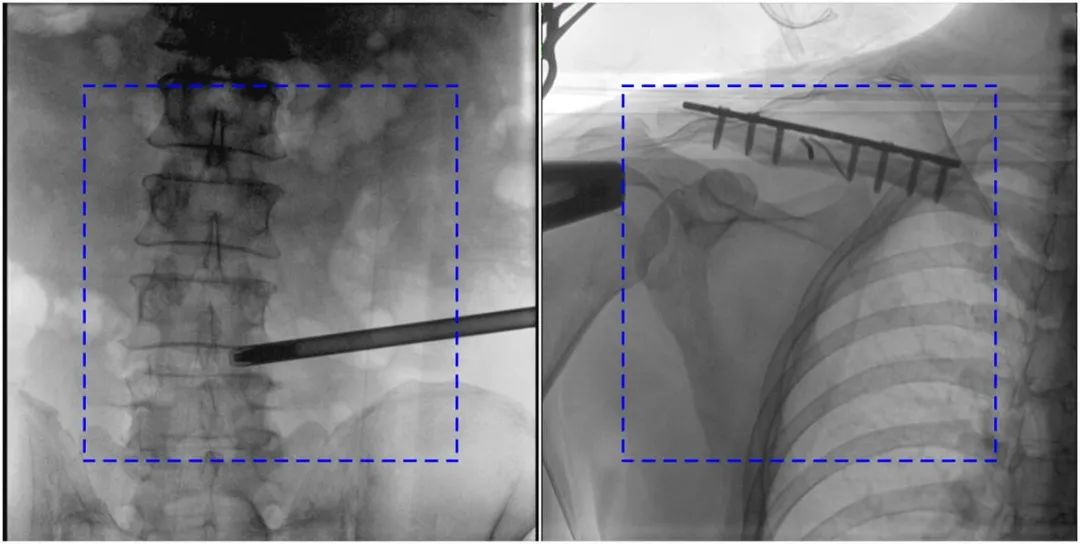

PLX119C臨床圖像與傳統(tǒng)圖像對比

注:藍色虛線內(nèi)為傳統(tǒng)21CM×21CM平板的成像區(qū)域。